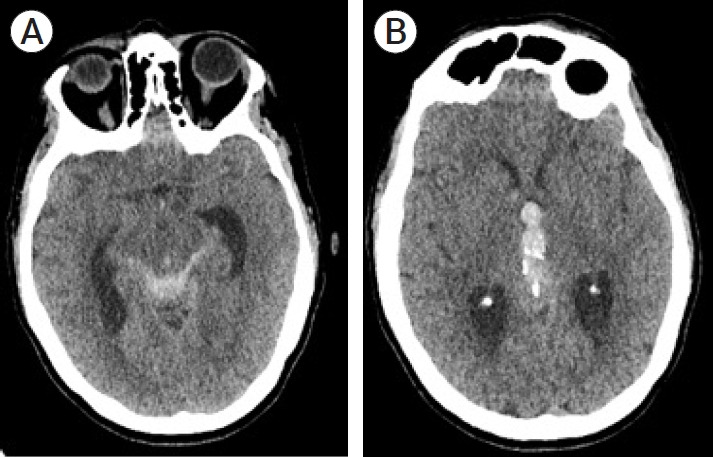

Aneurysms of the pineal region are rare and theoretically could arise from the medial posterior choroidal artery (MPChoA) or lateral posterior choroidal arteries (LPChoA). A 64-year-old lady with subarachnoid haemorrhage (SAH) and intraventricular haemorrhage (IVH) due to a ruptured MPChoA aneurysm was treated with microsurgical aneurysm excision via an occipital interhemispheric approach. This case demonstrates the importance of being mindful of rare aneurysm locations when initial vascular imaging in SAH appears normal.

松果体区域的动脉瘤是罕见的,理论上可能起源于内侧后脉络膜动脉(MPChoA)或外侧后脉络膜动脉(LPChoA)。一位64岁的女性因MPChoA动脉瘤破裂而出现蛛网膜下腔出血(SAH)和脑室内出血(IVH),经枕半球间入路行显微手术切除动脉瘤。本病例表明,当SAH的初始血管成像显示正常时,注意罕见动脉瘤位置的重要性。